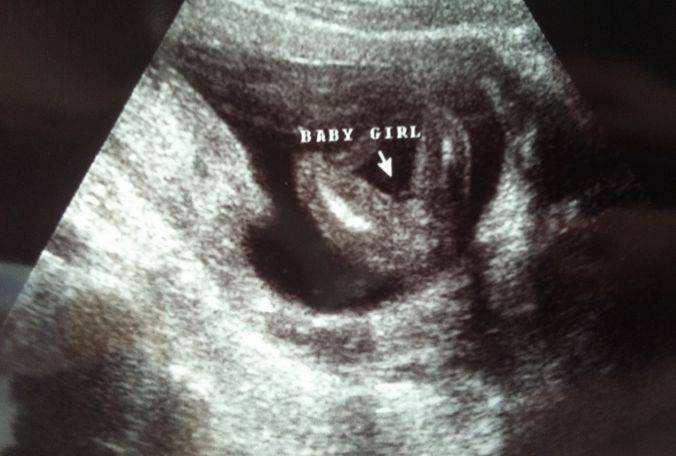

新加坡重男轻女也不严重,在产检的时候,医生会明确告知婴儿性别,除非你想要一个惊喜,不想知道。

而且,如果是胎位正显示清晰,十足确认的情况下,还会把性别白纸黑字写入报告,并不是暗戳戳、悄咪咪的告诉你。